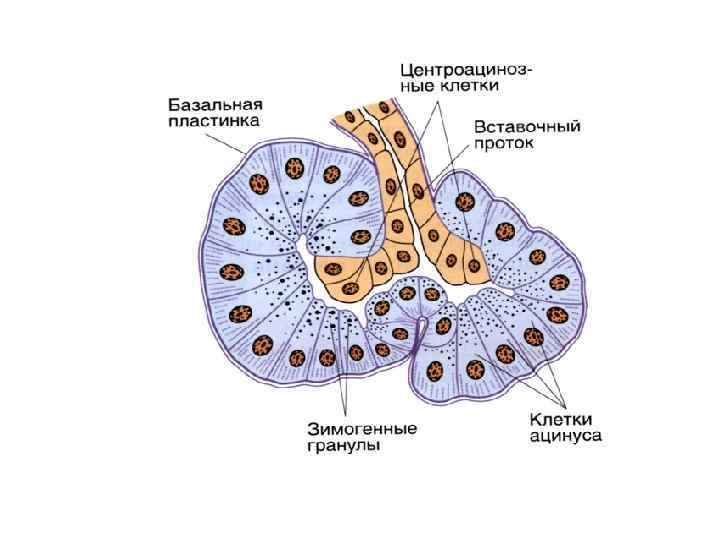

ПОДЖЕЛУДОЧНАЯ ЖЕЛЕЗА

Межацинарный проток

Ацинус и вставочный проток поджелудочной железы

Ациноциты и центроацинозная клетка

Вставочный и межацинарный протоки поджелудочной железы

Зимогенные гранулы